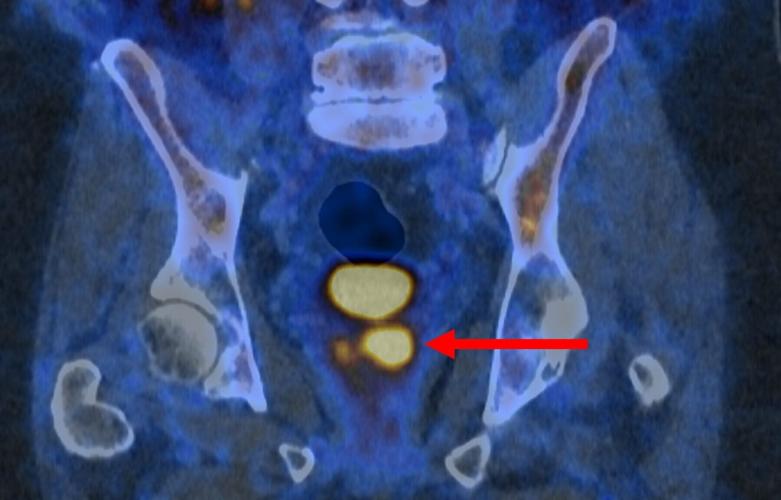

Glowing prostate cancer cells PSMA PET 2. (PRIMARY 2 via SWNS)

The PSMA PET/CT scan identifies more aggressive prostate cancer cells, which are potentially harmful and may need treatment.

It does so with a molecule that binds to prostate cancer cells and causes them to "light up in a remarkable way" - appearing as bright spots in the scanning image.

Dr. James Buteau, a nuclear medicine physician at the Peter MacCallum Cancer Centre, said: “PSMA PET/CT scanning makes prostate cancer cells light up in a remarkable way, particularly in more aggressive cancers.

"It’s rare to see such strong imaging that could be so powerful in the clinic.